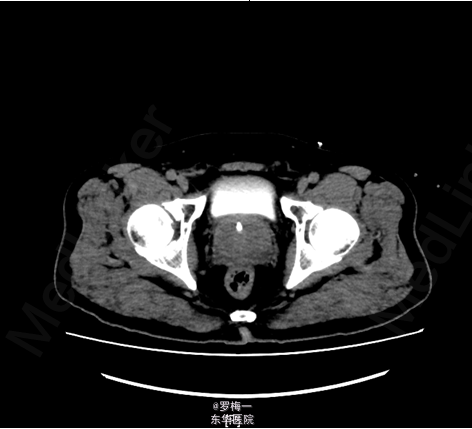

住院后完善相关检查,PSA两项均升高,其他各项术前常规检查未见明确手术禁忌证。遂于2015-04-02行经直肠前列腺穿刺活检,病理提示“符合前列腺增生伴慢性炎”。盆腔MR平扫+增强扫描考虑膀胱癌复发可能性大;彩超肝胆胰脾及核素骨扫描暂未见肿瘤远处转移证据。